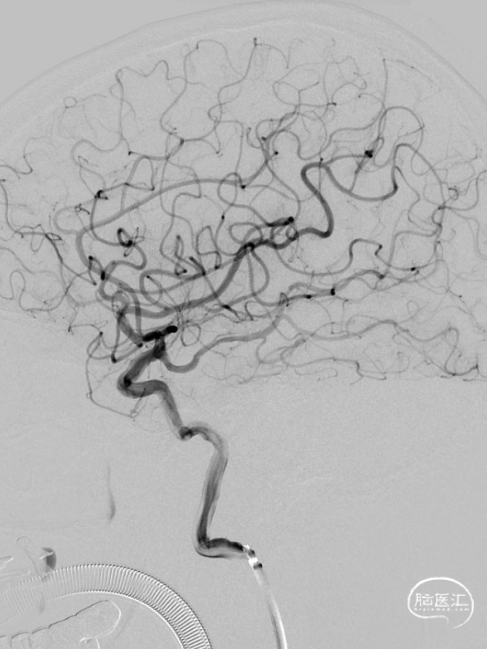

复查造影见支架展开良好,支架内及远端血流通畅,TICI分级3级。术顺,术毕,Proglide缝合术口。

术后第一天复查颅脑CT未见异常染色及大面低密度病灶。

查头颅MRI:右侧基底节区、右侧顶颞岛叶急性脑梗死。